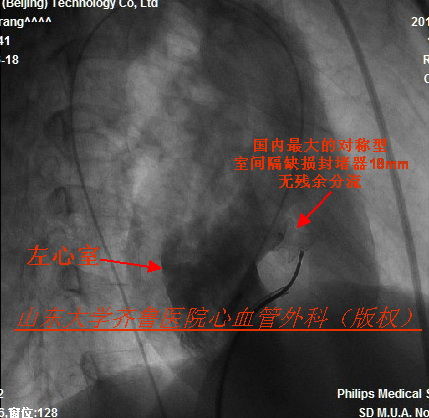

镜像右位心室间隔缺损封堵术一例ppt课件

右位心室间隔缺损的介入封堵治疗